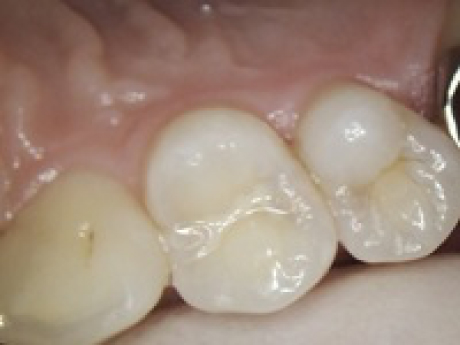

case1